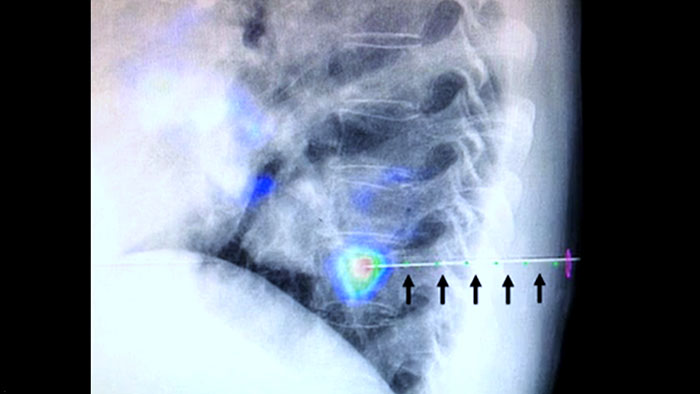

XperGuide proporciona una orientación por imágenes en tiempo real extremadamente preciso de cada aguja a una posición objetivo mediante la superposición de trayectorias preplanificadas con imágenes fluoroscópicas3.

La heterogeneidad de la lesión y la falta de notoriedad limitan la calidad de las muestras, así como la viabilidad de las biopsias cuando se realizan mediante ecografía o CT convencional. Con el aumento de la adopción de programas de detección en los pulmones, se han detectado cánceres pulmonares incipientes que se manifiestan como nódulos pequeños con mayor frecuencia que antes. Se observó que el 14.5% de una población seleccionada tenía nódulos ≤10 mm1-2. Nuestra tecnología de navegación guiada por aguja con CBCT aumenta la precisión y permite la selección de lesiones más pequeñas (<=1 cm) o heterogéneas, con mayor precisión con menos reposicionamiento de la aguja y menos dosis que la TC convencional.

La ablación percutánea (radiofrecuencia, microondas y crioablación) es un tratamiento mínimamente invasivo de eficacia comprobada de tumores renales, hepáticos, pulmonares y óseos. Es fundamental definir los límites del tumor y decidir un número óptimo de agujas y la trayectoria de la aguja correspondiente para poder realizar un tratamiento tumoral completo y no causar daños en el tejido circundante. Navegar con precisión en dosis bajas hacia la lesión de interés sin necesidad de cambiar la posición de la aguja aumenta la oportunidad de éxito y reduce el riesgo de complicaciones en las biopsias o ablaciones. La confirmación del criterio de valoración del tratamiento de ablación se puede lograr con imágenes 3D mientras el paciente aún se encuentra en la mesa.